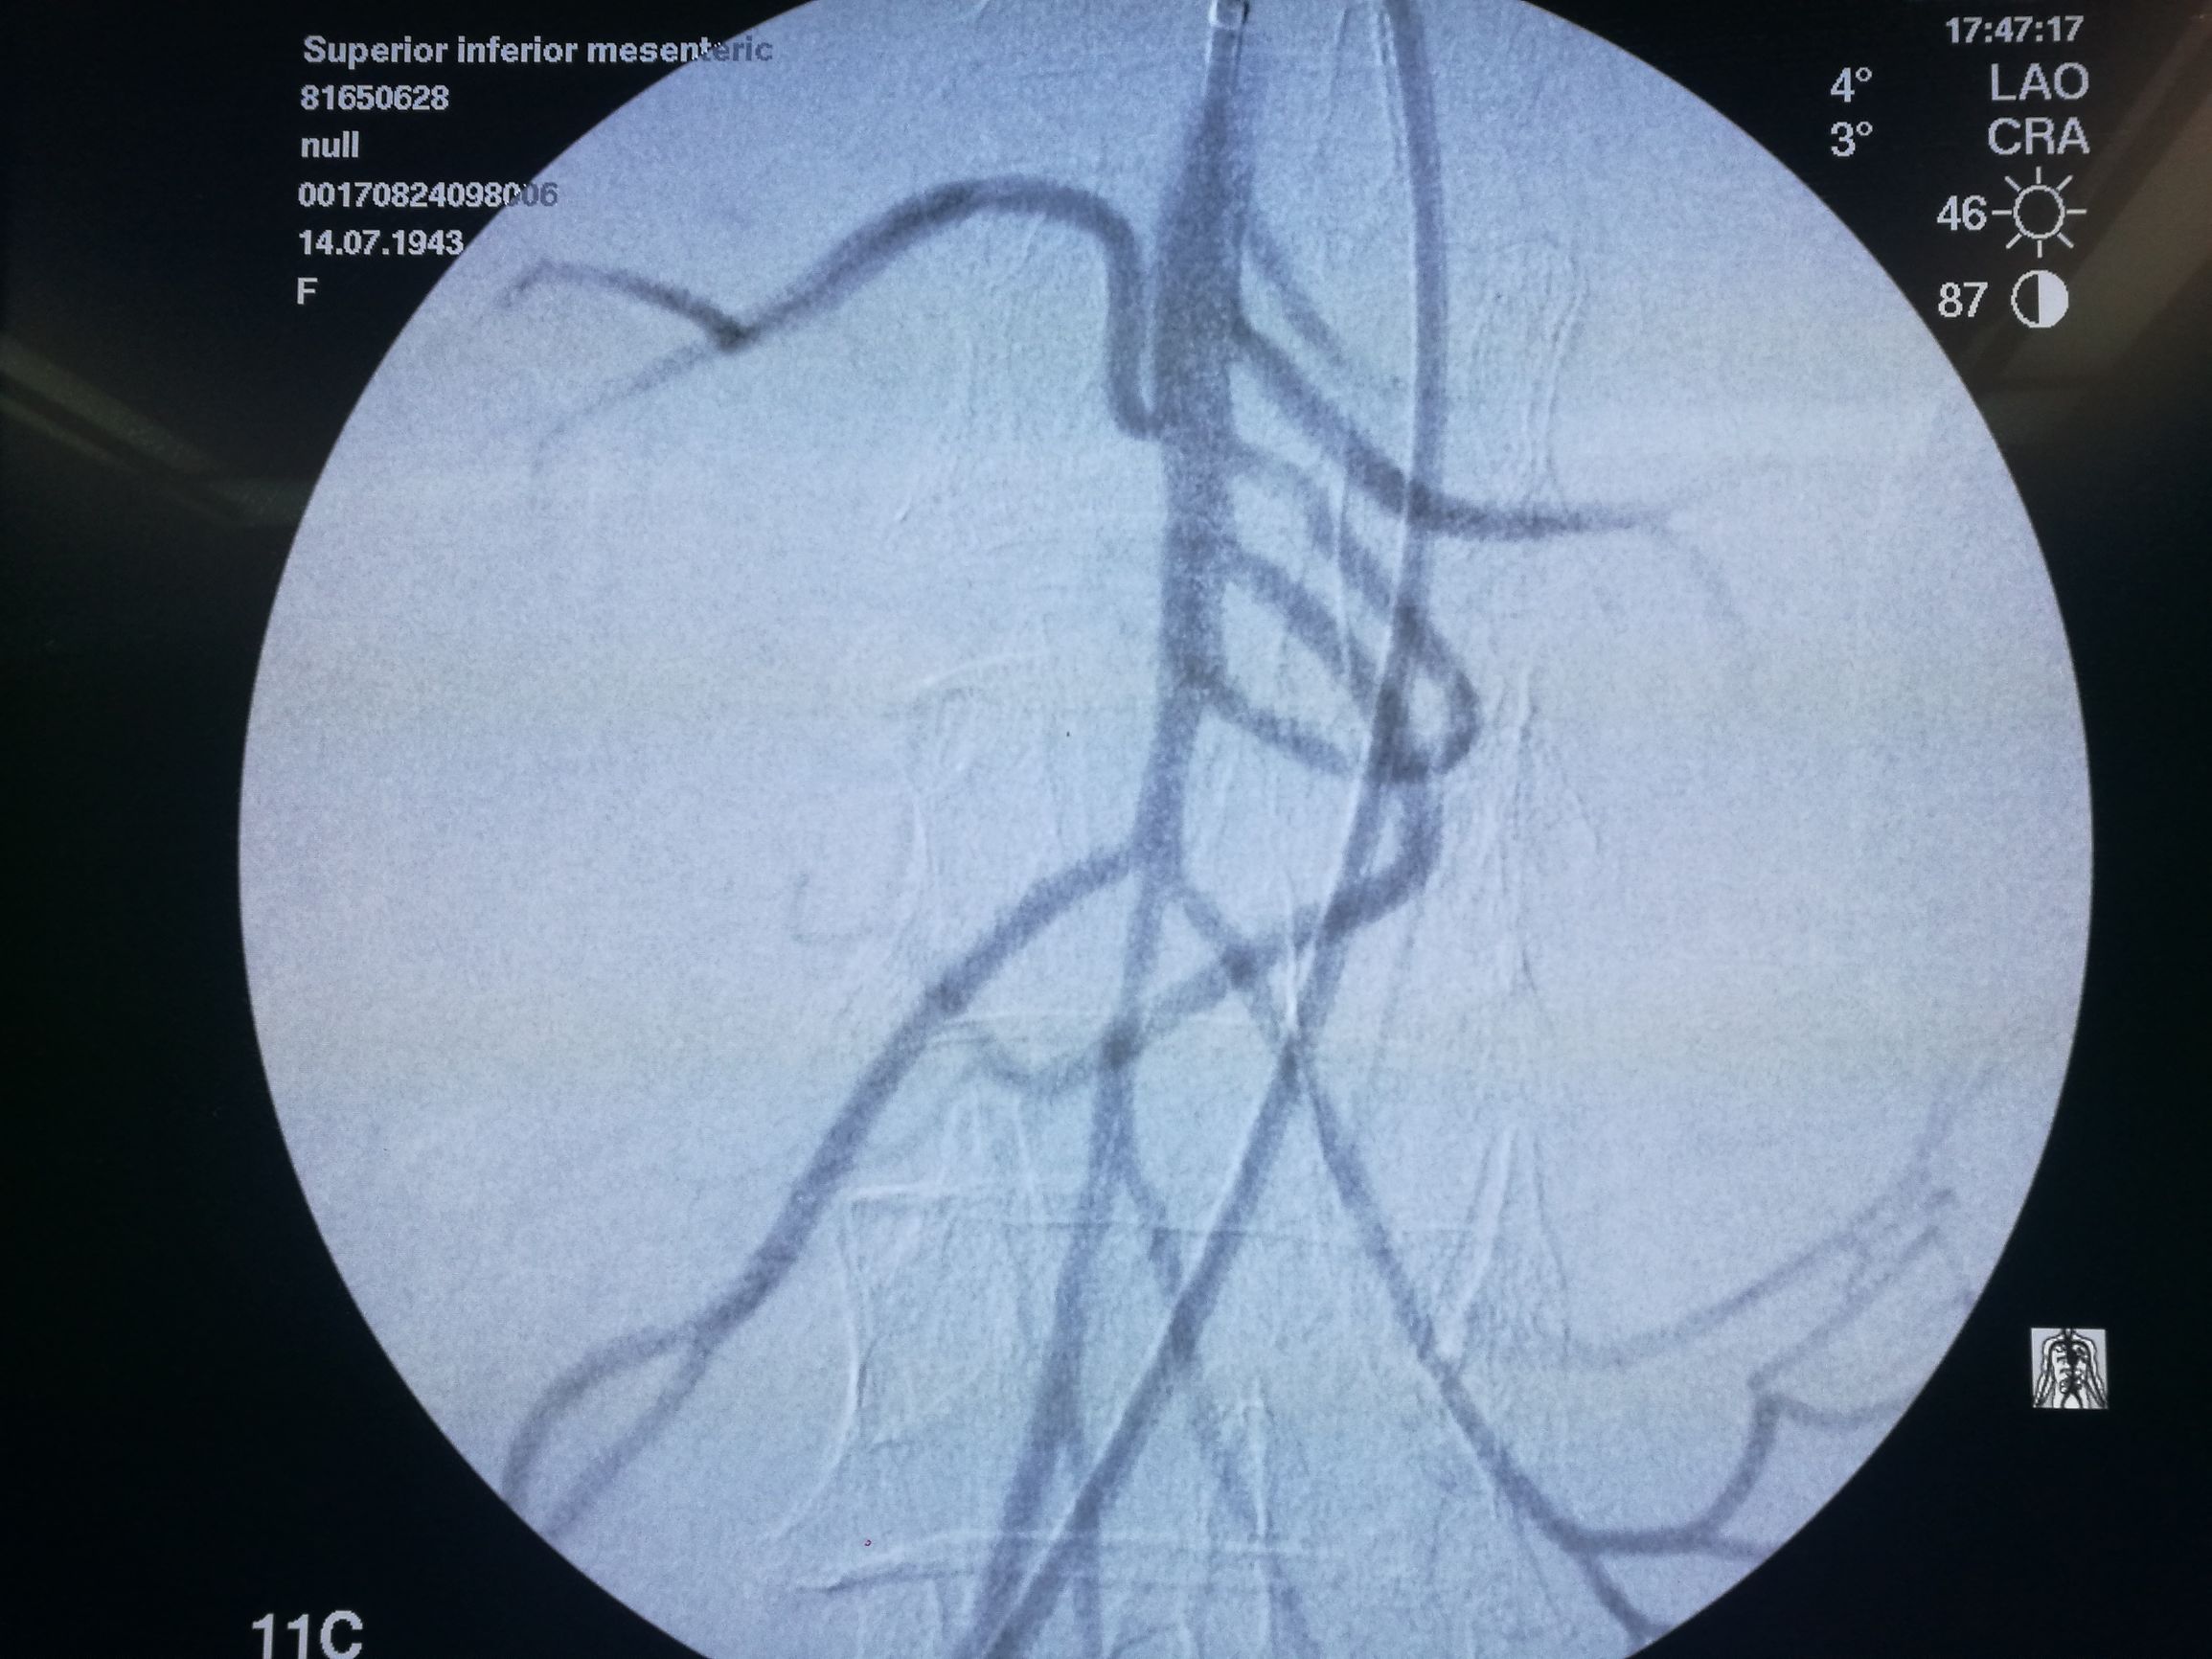

在局麻下经右侧股动脉穿刺,导管选入肠系膜上动脉造影,可见腔内充盈缺损(图3)。

图3. 肠系膜上动脉造影,可见管腔内充盈缺损,局部主干中断